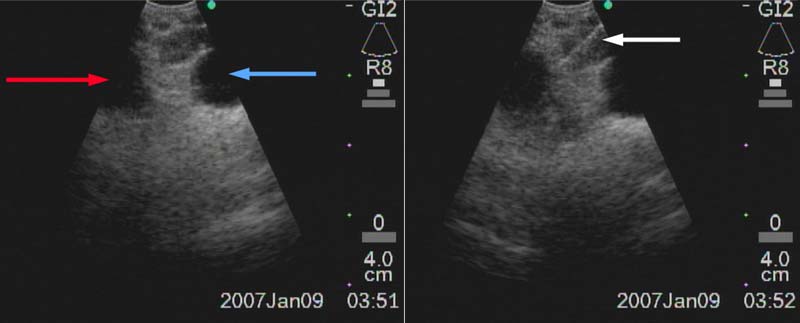

Figure 9: Right paratracheal node (4R) between truncus anterior of R PA (red arrow) and azygos vein (blue arrow). Biopsy needle is advanced through the node (white arrow).